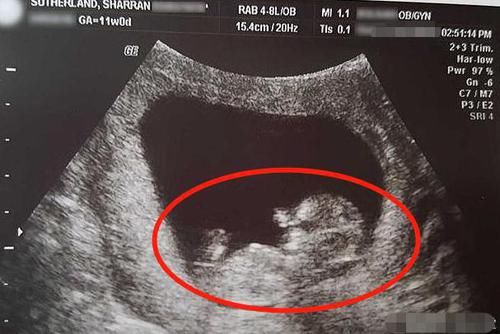

B超看男女几个月最准 怀孕十四周看胎儿男女准吗 第二人生

近14周 能瞧出来是男宝还是女宝吗 宝宝树

怀孕十四周胎儿男女图 搜狗图片搜索